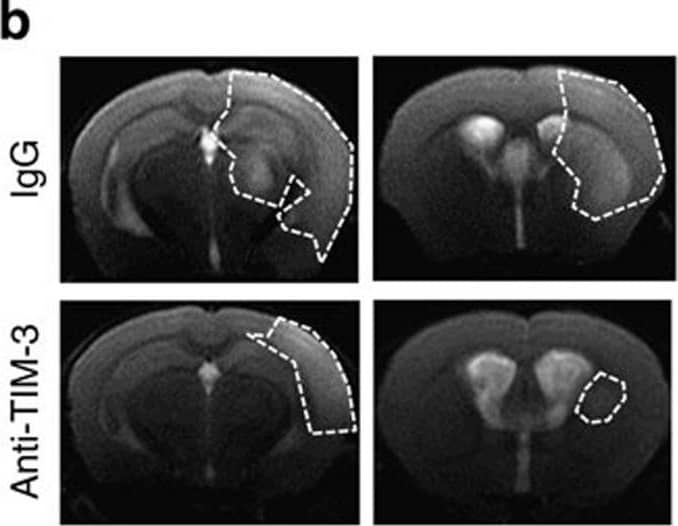

Blocking TIM-3 significantly reduces brain injury after hypoxia-ischaemia.(a) Representative images of TTC-stained brain slices from H/I mice treated with 100 μg of IgG (n=12) or anti-TIM-3 antibody (n=12). The infarct volume was quantified with Image J analyser and expressed as a percentage of the damaged ipsilateral hemisphere. (b) Representative magnetic resonance images (MRIs) from TIM-3-antibody-treated mice (n=4) and IgG-treated mice (n=4) at 24 h post-H/I. (c) Representative T2 images from TIM-3-antibody-treated mice (n=4) and IgG-treated mice (n=4) after H/I. (d) The extent of the oedema formation was obtained from the T2-weighted MRI images and ADC map. (e) Representative confocal microscopic images of immunohistochemical staining for NeuN and cleaved caspase-3 in coronal brain sections from IgG- and anti-TIM-3-treated H/I mice 24 h after injury. Scale bar, 50 μm. The graph shows the mean number of NeuN and cleaved caspase-3-stained cells per mm2. (f) Immunoblot detection of full-length PARP proteins in contralateral and ipsilateral cortex regions of control IgG- or anti-TIM-3-treated mice. The graph shows the relative levels of full-length PARP (116 kDa). Data represent the mean±s.d. from at least three independent experiments. Image collected and cropped by CiteAb from the following publication (https://pubmed.ncbi.nlm.nih.gov/25790768), licensed under a CC-BY license. Not internally tested by R&D Systems.